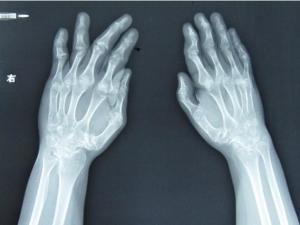

8.X线检查

早期表现为关节周围软组织肿胀和关节腔渗液,病变进一步发展则关节旁骨质疏松、关节软骨消失、骨质侵袭和关节骨性强直畸形。